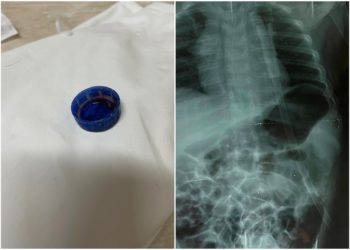

Un copil de trei ani a ajuns la spital în stare extrem de gravă, după ce a înghițit un capac ...